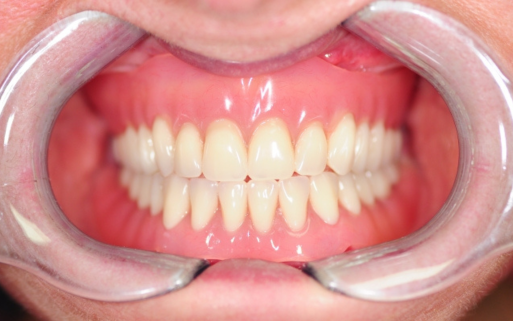

Na implancie lokuje się ceramiczną koronę, którą ujednolica się z pozostałymi zębami - wygląda więc jak naturalny ząb.

Dzięki temu, że implanty zębów są najbardziej komfortowym i najtrwalszym rozwiązaniem zbliżonym do naturalności, pacjent zapomina, że w ogóle je posiada.

Lepsza estetyka – Implanty wyglądają jak naturalne zęby i są bardziej estetyczne niż protezy.

Przed i Po Naszych Klientów